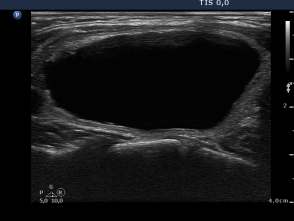

Three month prior to sclerotherapy (1st row of images)

Clinical presentation: a 50-year-old woman noticed a lump in the neck for 3 months. Thesize of the lesion did not changed over time.

Palpation: a firm nodule in the left lobe. The lesion was painless.

Functional state: euthyroidism with TSH 1.08 mIU/L.

Ultrasonography: the thyroids were echonormal. A large central-type cyst occupied almost the entire left lobe.

We tried to remove the cystic fluid but only 1.5 ml brown gelatinous fluid could be aspirated. Aspiration cytology resulted in benign cystic lesion.

We suggested a repeat aspiration 3 months later.